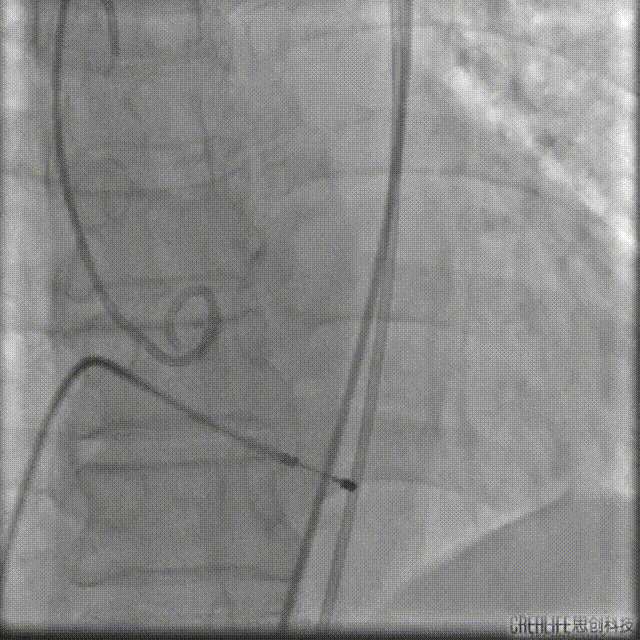

导丝跨瓣

选择22mm球囊进行预扩,结果显示具有明显腰征,无瓣周反流,遂即选择TaurusElite 26mm瓣膜,凭借其优异的柔顺性,轻松完成过弓。

球囊预扩

TaurusElite顺利过弓